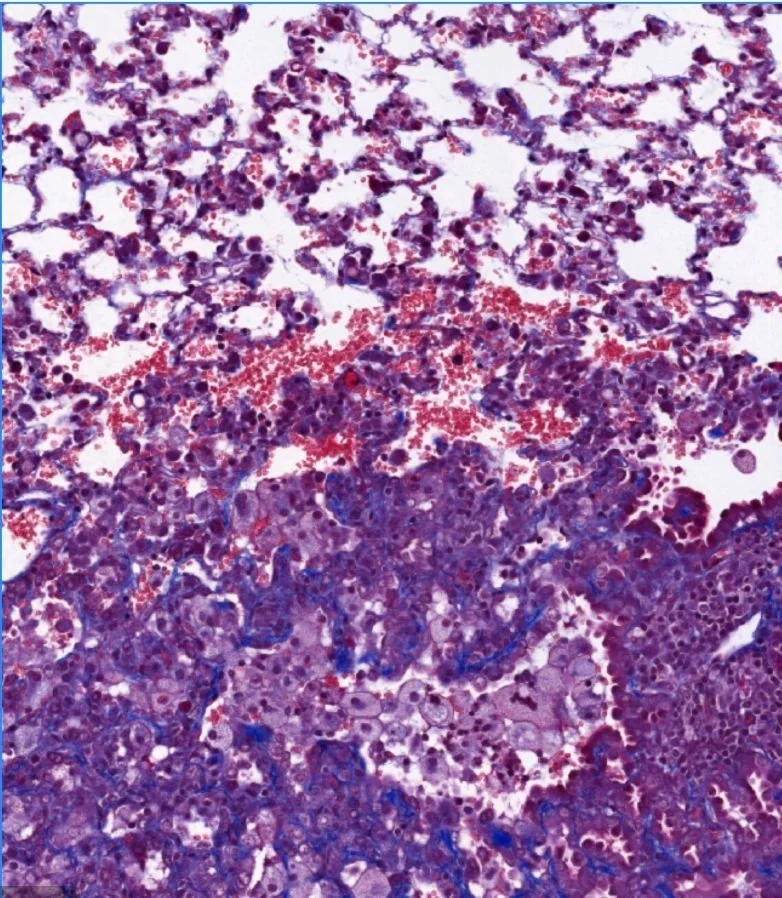

Pathogenesis of acute and chronic tissue damage in TB infection

Although most TB research is focused on the period of active infection, it is increasingly recognized that up to 50% of the morbidity and mortality associated with TB infection is a result of the chronic tissue damage left after infection is cured. Given the global burden of tuberculosis, TB is arguably the leading cause of pulmonary fibrosis around the world. Our understanding of the mechanisms through which acute tissue damage and chronic fibrotic changes occur during TB infection are largely unknown. Using a mouse model, we are interested in understanding the contributors to acute and chronic tissue damage in TB infection and how novel therapies might improve functional outcomes after successful antibiotic treatment.